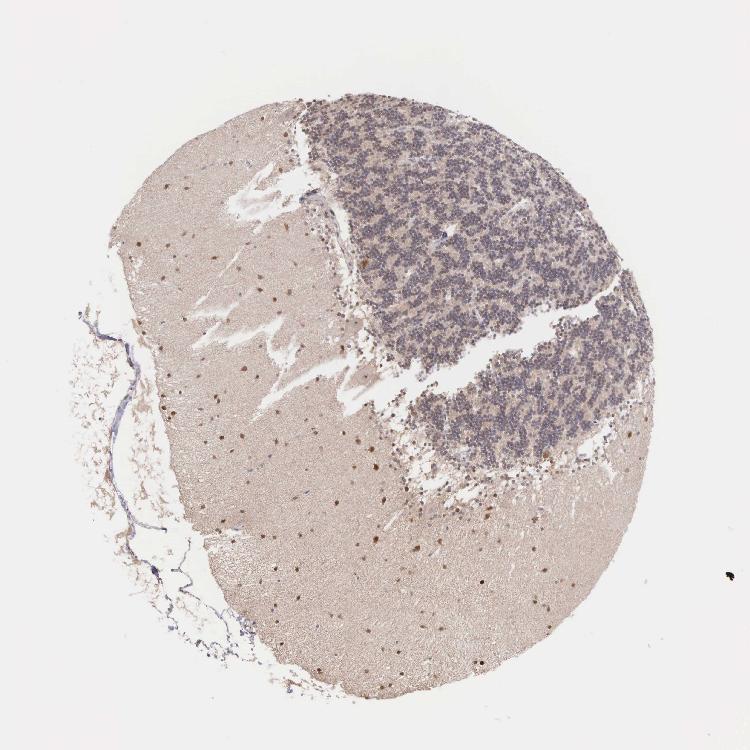

CEREBELLUM - Antibody stainingi

Antibody staining in the annotated cell types in the current human tissue is reported as not detected, low, medium, or high, based on conventional immunohistochemistry profiling in selected tissues. This score is based on the combination of the staining intensity and fraction of stained cells.

Each image is clickable and will lead to virtual microscopy that enables deeper exploration of all samples and also displays staining intensity scores, fraction scores and subcellular localization as well as patient and tissue information for each sample.

Antibody HPA000804

Purkinje cells Medium

Cells in granular layer Medium

Cells in molecular layer High